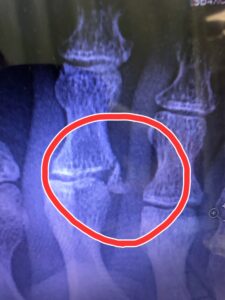

嫁骨折。

嫁と息子が相撲を取り、嫁が勝ったのですがその際足の上に息子が乗ってしまい、右第2趾を骨折してしまいました😭